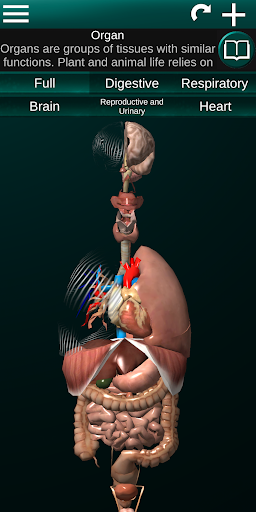

Menampilkan model anatomi 3D dari organ utama tubuh manusia dan penjelasannya masing-masing.

Apa yang ada di aplikasi?

* Sistem pencernaan, termasuk lambung, usus kecil, usus besar, dan animasi sistem ini.

* Sistem pernafasan, yang meliputi trakea, bronkus, paru-paru dan animasi sistem ini.

* Sistem reproduksi, yang meliputi organ reproduksi pria dan wanita.

* Otak, yang meliputi otak, otak kecil, dan batang otak.

* Jantung, yang meliputi atrium, ventrikel, aorta, dan animasi organ ini.